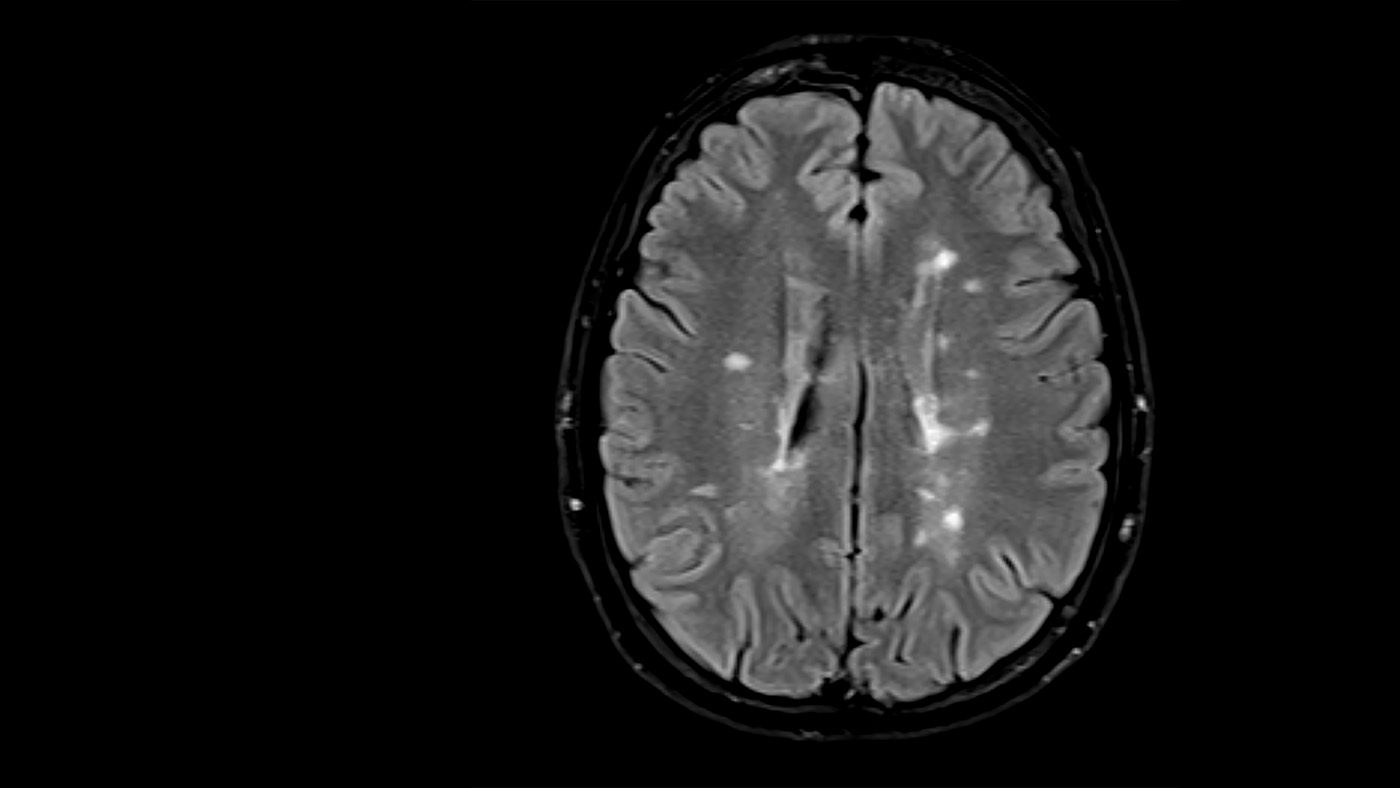

Machine Learning Image Reconstruction: image of a brain scan

The acquisition of raw data for medical images is often time consuming or harmful to patients. Algorithms and techniques that allow us to reconstruct images from datasets that are under-sampled or corrupted by artifacts can enable an improved patient experience and reduce costs. At Microsoft we are engaged in the development of machine learning models that facilitate accelerated imaging. We have enhanced the InnerEye (opens in new tab) toolkit to support training of reconstruction models. Specifically, we are providing dedicated tooling to enable the use of the FastMRI (opens in new tab) dataset and existing model architectures. This includes tooling for managing the large MRI raw datasets needed for training the models. We have also published clinical annotations (opens in new tab) that enable evaluation of new models in the context of pathology.